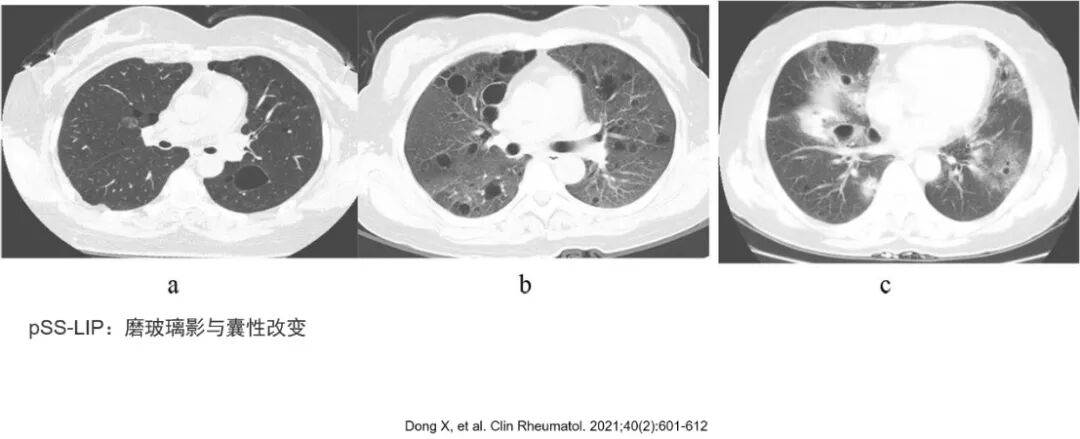

第二步,明确是否合并其他影像特征。在以GGO为主要表现的基础上,很多时候还合并小叶间隔增厚、牵拉支气管扩张、囊性改变以及结节影等。多种影像特征的结合有助于我们更准确地评估病理生理改变,以及缩小鉴别诊断范围。例如合并网格影,即我们常说的铺路石征(crazy-paving),其往往提示气腔或间质改变合并小叶间隔或小叶内间质增厚,除了常见的肺泡蛋白沉积症(原发或继发),浸润性黏液腺癌、吸入性类脂性肺炎以及一些病毒感染也可能出现类似表现。而一例细胞免疫缺陷患者特别是HIV感染患者,肺部影像学提示GGO及囊性改变,这是HIV合并肺孢子菌肺炎(PCP)的经典表现。而干燥综合征患者肺部出现GGO以及囊性改变,需警惕继发淋巴细胞性间质性肺炎(LIP)等淋巴增殖性疾病,其机制是在肺泡壁、支气管、细支气管周围淋巴细胞浸润,而细支气管处浸润的淋巴细胞聚集可引起局部支气管狭窄及活瓣效应。GGO合并牵拉性支气管扩张常见于间质性肺病或感染后支气管扩张。而GGO中心出现结节改变,部分学者将其命名为“煎蛋征”,是一些血管肉瘤、出血性转移瘤(绒癌、肾脏恶性肿瘤)以及病毒性肺炎的较特征影像改变。《肺部高分辨率CT》一书对这部分内容有详细的阐述,需要注意的是,如果肺部影像学以结节实变等其他的影像征象为主,建议以主要征象开展影像鉴别诊断。